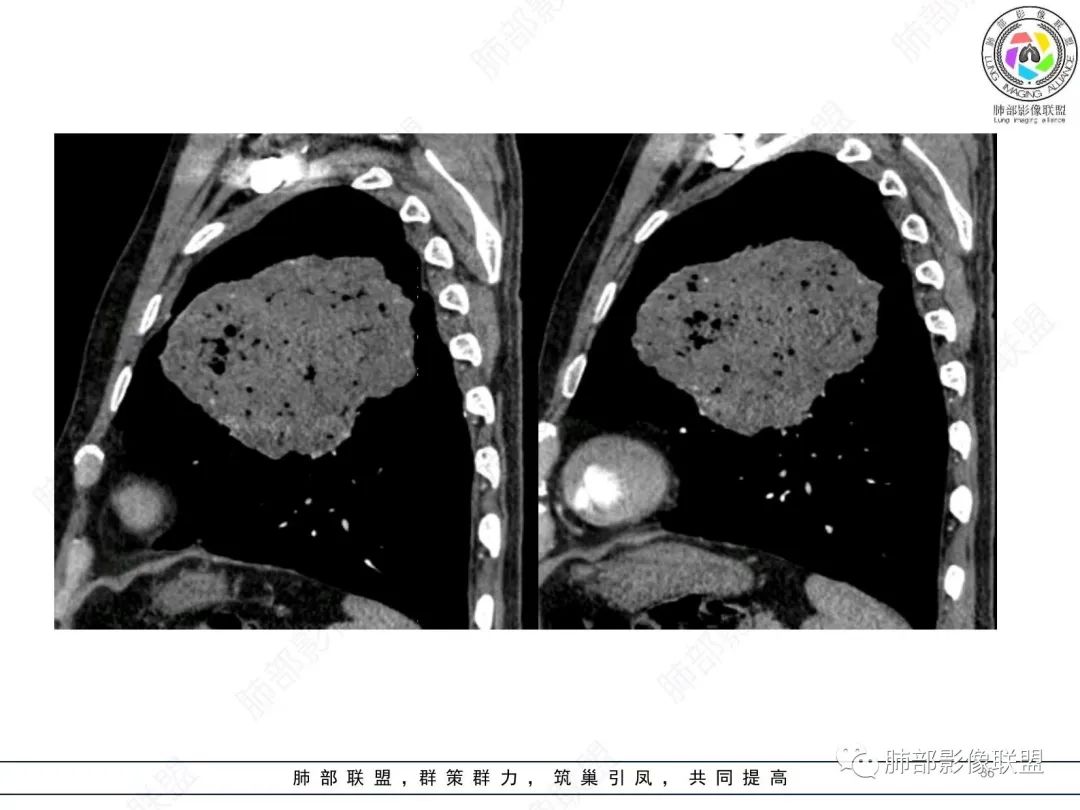

左肺上叶大肿块,膨胀性生长,边界清,密度较低,见部分坏死区,强化弱,肿块见支气管充气V扩张征,分布僵直,枯树枝特点,另一个重要特点血管造影征,淋巴瘤,肿块长轴与胸膜平行,与隐球菌鉴别,隐球荚膜抗原检查,明确诊断经皮肺穿刺。另胸膜钙化(问诊既往有无患胸膜炎病史)。

左肺上叶胸膜下肿块,宽基底与胸膜相连,跨叶裂,边缘清晰膨隆,其内支气管充气,部分扩张、僵直,无明显强化,血管造影征,考虑淋巴瘤,鉴别腺癌

左肺胸膜下巨大占位,跨叶裂,宽基底与胸膜相连,胸膜钙化,平扫密度较低,强化不明显,可见内部血管显影,支气管充气征和扩张,考虑为恶性,倾向于淋巴瘤

支持淋巴瘤,左上肺大肿块,有分叶,边缘光整,病灶内密度不均,可见支气管扩张征,增强后可见血管影征。周围肺野清晰。

左肺上叶肿块,宽基底与胸膜相连,跨叶裂,边缘清晰膨隆,可见小分叶,其内支气管充气,部分扩张、僵直,呈枯枝征,支气管达边征,增强无明显强化,可见血管造影征,考虑恶性病变,淋巴瘤,鉴别粘液腺癌。

大肿块,边缘光滑,深分叶

近端支气管堵塞、推移为主

部分类似于脐凹征

内部支气管扩张

肺动脉推移为主,边缘部分进入

1)部位:周围型或中央型软组织肿块,以周围型为多见,且肿瘤多位于肺上叶。如本例:该肿瘤位于左肺上叶。

2)大小及形态:由于本病恶性程度高,早期症状不明显,发现时肿块均较大。如本例病变巨大。

3)肿块边界和边缘:多较清楚,呈圆形、类圆形,且由于肿块生长速度不均匀,可见分叶,毛刺少见。有报道肿块周围毛玻璃影是多形性癌特征表现。

4)密度:肿块平扫为软组织密度,由于体积较大,内部常见大片状坏死,可出现不规则厚壁空洞或坏死内多发无壁小空洞,坏死多不均匀:坏死灶内可见如柳絮样的斑片样强化灶,坏死边缘与非坏死区分界不清本例坏死较明显,密度不均匀。

5)肿瘤强化方式:肺部恶性肿瘤强化程度与其血供丰富程度相关,血供丰富多强化明显,反之则较差。由于PSC 周边实性部分富血供及内部黏液变性、坏死,增强后肿块多数呈轻-中度边缘环形强化或不均匀小斑片状强化。国外学者对照病理发现肿瘤细胞或胶原组织增强扫描时强化,无强化的低密度区代表了黏液样变性区和出血坏死区。